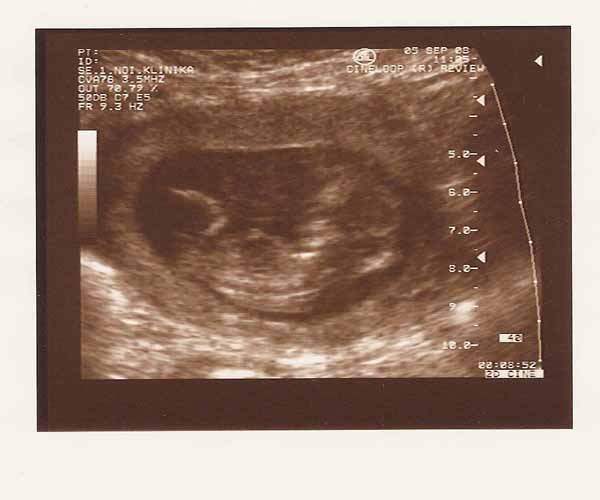

Bea neked is mekkora már a pocakod!

De itt sokkal fiatalabbnak tűnsz nekem. Ha még mosolyogsz is, el sem hisszük, hogy leérettségiztél már. Nagyon csini vagy. A pocak meg azért látszik, hogy növöget.